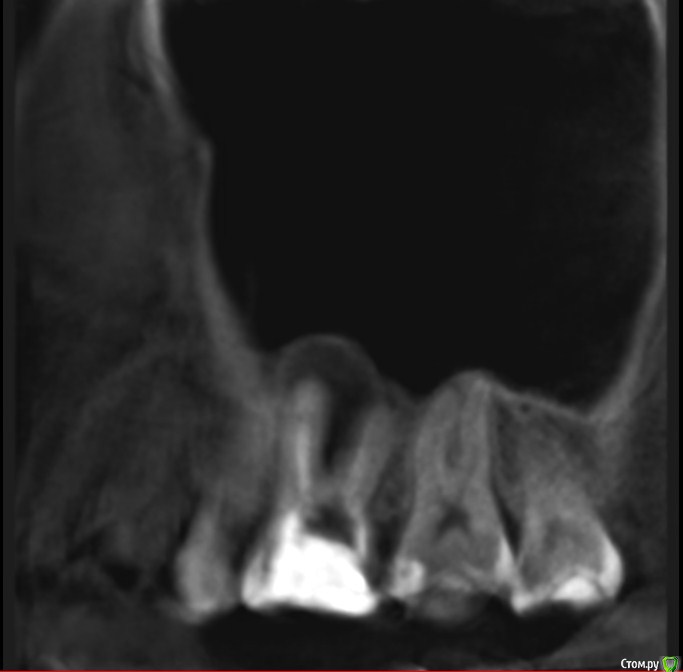

Здравствуйте! Мне показано удаление из-за кисты.

Беспокоит зуб очень редко: при жевании жесткого возникает боль, затем ноет, даже больше пульсирует, а потом еще как бы чешется внутри, где десна. Бывает, что левая ноздря-пазуха как бы "пощипывает", и как бы подзакладывает, но при этом нос дышит нормально.

Собираюсь, не откладывая до прорыва в гайморову пазуху, обратиться за лечением-решением этого моего вопроса со здоровьем.

Подскажите, пожалуйста, точно удалять? Как принять это решение, все таки надежда на какой то другой лечебный вариант теплится =)post-59509-0-08196600-1578493080_thumb.jpgpost-59509-0-63211400-1578493088_thumb.jpgpost-59509-0-77705800-1578493096_thumb.jpgpost-59509-0-02698500-1578493106_thumb.jpgpost-59509-0-04880900-1578493120_thumb.jpgpost-59509-0-11411000-1578493128_thumb.jpg

Найдите терапевта, занимающегося эндодонтическим лечением зубов с использованием микроскопа. Окончательный вердикт все равно можно выдать только взглянув через увеличение в сам зуб.

По представленным срезам создаётся впечатление, что лечение вполне возможно